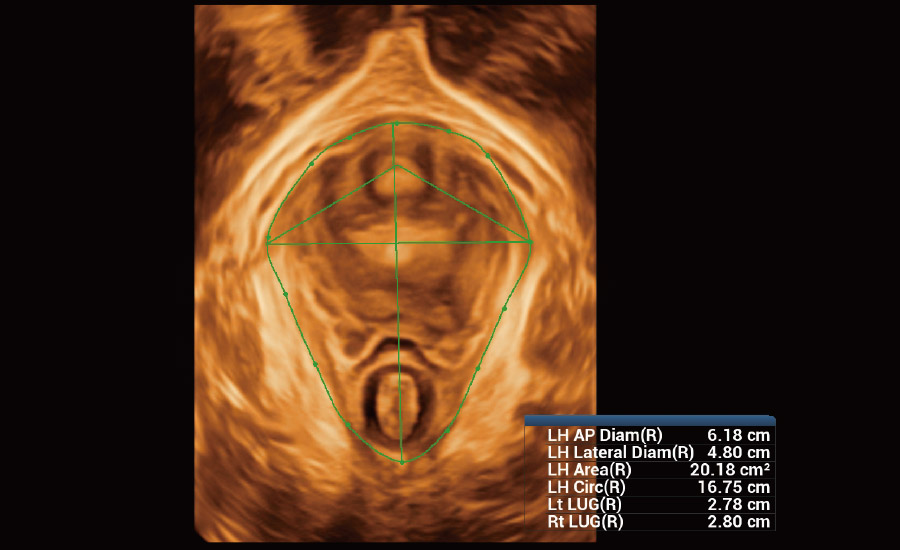

Informa??es abrangentes adaptadas aos cenƔrios

Por meio da combina??o de algoritmos avan?ados e do conhecimento especĆfico da regi?o, a inovadora solu??o Smart Scene permite a identifica??o automĆ”tica das caracterĆsticas do tecido e fornece diagnĆ³stico especĆfico dos Ć³rg?os com informa??es completas. Com base na identifica??o automĆ”tica de cenĆ”rios, a solu??o realiza n?o apenas a varredura 2D inteligente com configura??es e medidas automĆ”ticas, mas tambĆ©m oferece informa??es 3D abrangentes em todas as etapas, desde a otimiza??o de imagens volumĆ©tricas atĆ© a difĆcil obten??o de planos 2D, e a quantifica??o durante todo o procedimento. Ele ajuda a reduzir em grande parte a dependĆŖncia de habilidades clĆnicas, ao mesmo tempo que aumenta a precis?o, a confian?a e a eficiĆŖncia no diagnĆ³stico.

- Cuidando da saĆŗde da mulher com solu??es em ginecologia e uroginecologia

Uroginecologia